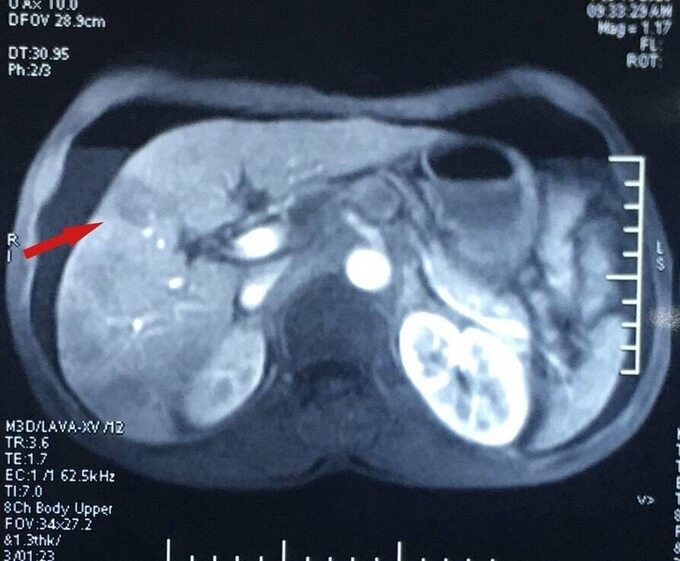

Tại Bệnh viện Ung Bướu Hà Nội, các kết quả cận lâm sàng cho thấy, dày thành thực quản 1/3 dưới tạo khối kích thước 5x2.5 cm, thâm nhiễm mỡ xung quanh, có nhiều hạch quanh tổn thương, kích thước hạch lớn nhất 2 cm.

Đặc biệt, ung thư đã di căn gan với ổ lớn nhất đường kính 3 cm. Giai đoạn này, các biện pháp điều trị tại chỗ không khả thi. Bệnh nhân được chỉ định điều trị hóa chất toàn thân.